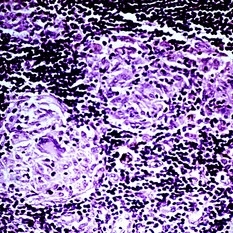

Slide 5-34 Slide 5-34Feb 25 2019 by Lancaster Course in Ophthalmology Large nuclei of an ulceronodular basal cell carcinoma can be compared with the adjacent normal epithelial cell nuclei. Note the peripheral palisading of the nuclei around the edge of the tumor lobules. Condition/keywords: basal cell carcinoma of eyelid, epithelial, nuclei

Slide 5-35 Slide 5-35Feb 25 2019 by Lancaster Course in Ophthalmology Cords of infiltrating basal cells in the dense, fibrous stroma of a morphea type basal cell carcinoma. Condition/keywords: basal cell, basal cell carcinoma of eyelid, fibrous stroma